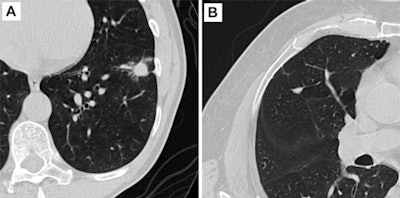

Axial CT images of pulmonary nodules. (A) Malignant nodule. (B) Benign nodule. Image and caption courtesy of the RSNA.

Axial CT images of pulmonary nodules. (A) Malignant nodule. (B) Benign nodule. Image and caption courtesy of the RSNA.Henschke and colleagues evaluated 20 years of study data, estimating lung cancer-specific survival regardless of treatment and categorized by lung cancer consistency on CT (solid, part-solid, and nonsolid). They found that the overall 20-year lung cancer survival rate for the 1,285 participants diagnosed with the disease was 80%.